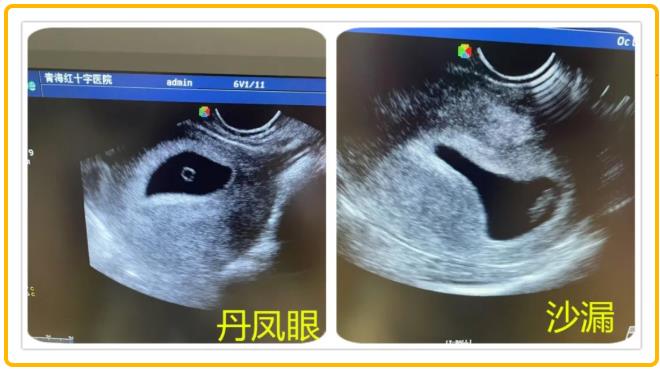

当超声探头的凝胶在腹部晕开涟漪,显示屏上的光斑便化作生命的星图。那些不足指甲盖大的孕囊,有的像春日里第一颗露珠,有的像蓝天下的云朵,还有的像时间的沙漏……“小豌豆”是六周的胚芽,绒毛膜正在形成玫瑰花瓣般的皱褶;“蒲公英”是八周的胚胎,羊膜腔里漂浮着绒毛的丝絮;“星星是意外停育的孕囊,却依然保持着完美的图形。

无影灯下,金属器械碰撞的清脆声中,总流淌着温柔的诗句。麻醉师在推注丙泊酚前会轻声念诵:“你原是银河的星子,偶然投影在春天的湖”,让患者在美妙的意象中沉入梦境。最特别的还是胚胎病理标本瓶,每个透明容器上都贴着名字:云朵、小水滴、水晶公主、沙漏、天平、创可贴……将无法言说的遗憾转化成语言的琥珀。它们用独特的存在方式告诉我们:生命是一段奇妙的旅程,每一段经历都值得我们珍惜,纵然逝去,也要留下温柔的印记。

请相信,当你为每一个孕囊轻轻唤作一个名字,它们便不再是冰冷的数据,而是有了温度的存在——那一刻,它们分外美丽,而你也不再孤单。